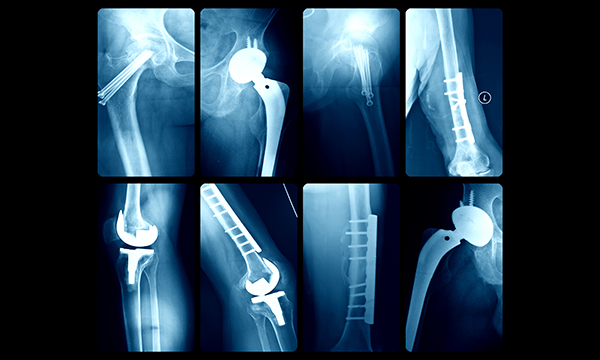

The use of benzodiazepines and related drugs increases the risk of hip fracture by 43% in people with Alzheimer’s disease, say researchers from the University of Eastern Finland.